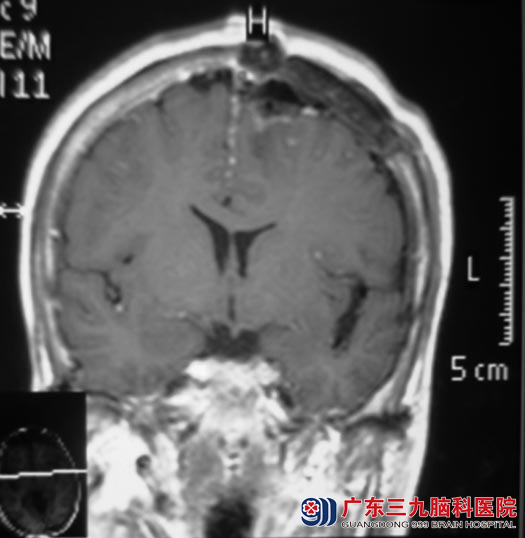

7月16日,鲁明主任主刀,在全麻下行左侧大脑镰窦旁脑膜瘤切除术,显微镜下见顶部肿瘤与硬膜粘连,包膜完整,质中偏硬,血运较丰富,广基与大脑镰相连。电凝切开肿瘤包膜,电灼、分离肿瘤,见肿瘤侵入上矢状窦内,肿瘤与脑组织粘连,镜下全切肿瘤,大小约4.5cm×4.9cm×3.5cm,术中对上矢状窦保护完好,手术顺利结束。陈阿姨已康复出院。术后病理结果为:(左侧大脑镰旁)砂粒体型脑膜瘤(WHO I级)。

▲手术后